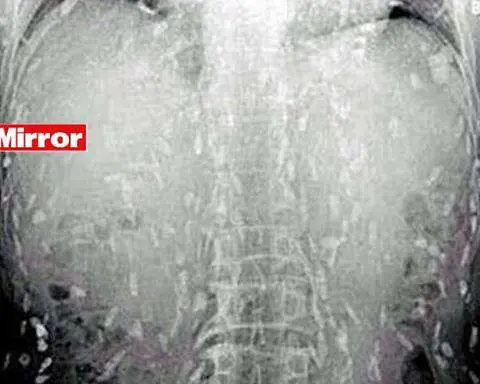

La risonanza magnetica ha portato alla scoperta di una situazione ormai critica: le larve del parassita avevano invaso la corteccia cerebrale, il cervelletto ed il tronco cerebrale del ragazzo, che non ha avuto scampo